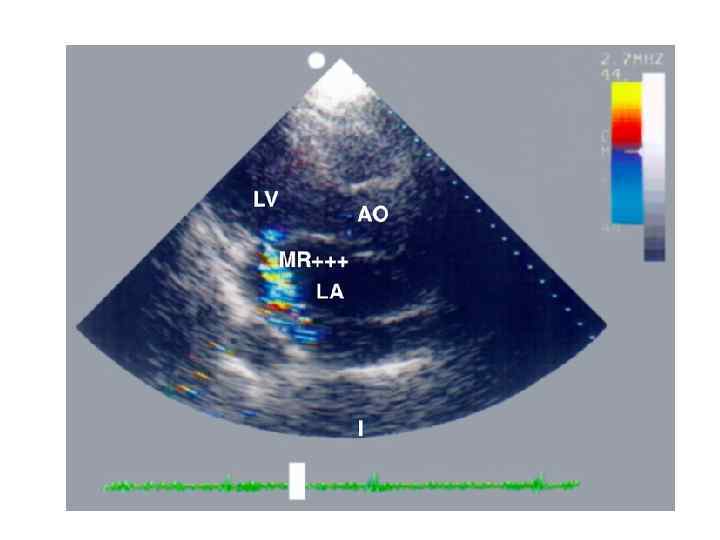

Недостаточность митрального клапана Insufficientia valvulae bicuspidalis (mitralis) — возникает в тех случаях, когда митральный клапан во время систолы левого желудочка не закрывает полностью левое атриовентрикулярное отверстие, вследствие чего происходит обратный ток (регургитация) крови из левого желудочка в левое предсердие.

Этиология – Миксоматозная дегенерация митрального клапана. – Хроническая ревматическая болезнь сердца. – Кальциноз митрального кольца. – Дисфункция папиллярных мышц при ИБС. – Инфекционный эндокардит. – Врожденные болезни соединительной ткани (синдром Марфана).